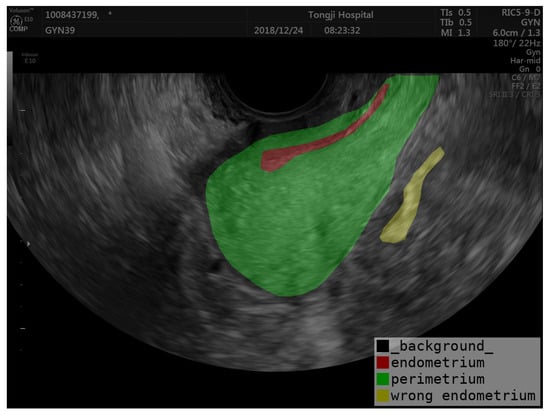

Accurate segmentation of the uterine ectoderm improves endometrial thickness measurements, crucial for diagnosing uterine diseases. For example, in the image below, the endometrium is incorrectly categorized as being outside the uterus (marked as yellow in Figure 5) due to the uneven echogenicity of the abnormal endometrium. The correct position of the endometrium should be shown as red in Figure 5. By segmenting the perimetrium (marked as green in Figure 5) of the uterus first, we can eliminate external interference and improve the accuracy of endometrial segmentation. Our method helps reduce errors from uneven echoes and unclear boundaries, leading to better diagnostic precision and patient outcomes. The semi-supervised learning framework also increases efficiency by using both labeled and unlabeled data, reducing the need for extensive manual annotations.

Figure 5. Example of endometrial prediction error.